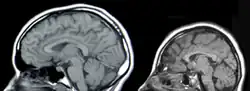

![]() MRI-billede af en normal (venstre) og en hjerne med en ASPM-mutation forårsaget af sygdommen | |